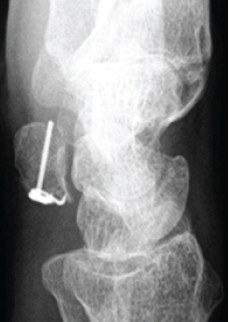

Navigation-Assisted Endoscopic Excision of Lumbar Vertebral Osteoid Osteoma: A Case Report

Ajit Hanmant Rampure , Ayush Sharma , Shubham Kadam , Nandan Marathe , Ajay Kumar , Sourav Lal Das .………………………………p.146-150